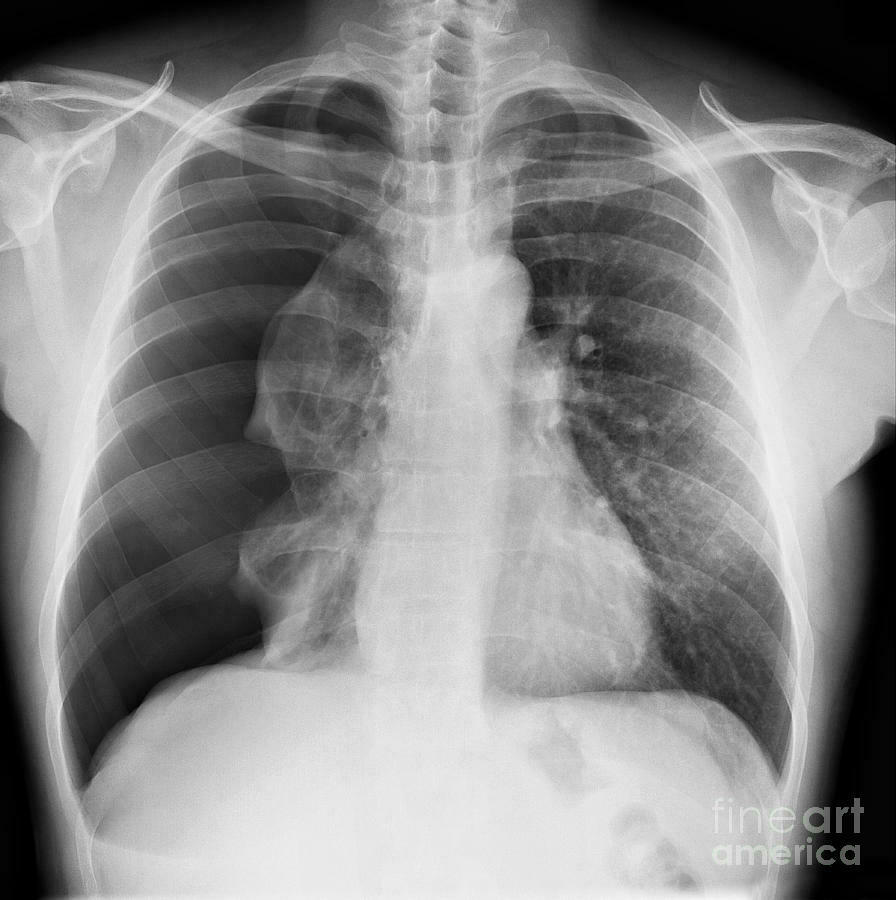

O que é o Sinal do Broncograma aéreo? Vias aéreas visíveis pela consolidação do pulmão (brônquios).

Qual sinal é esse? Sinal do broncograma aéreo